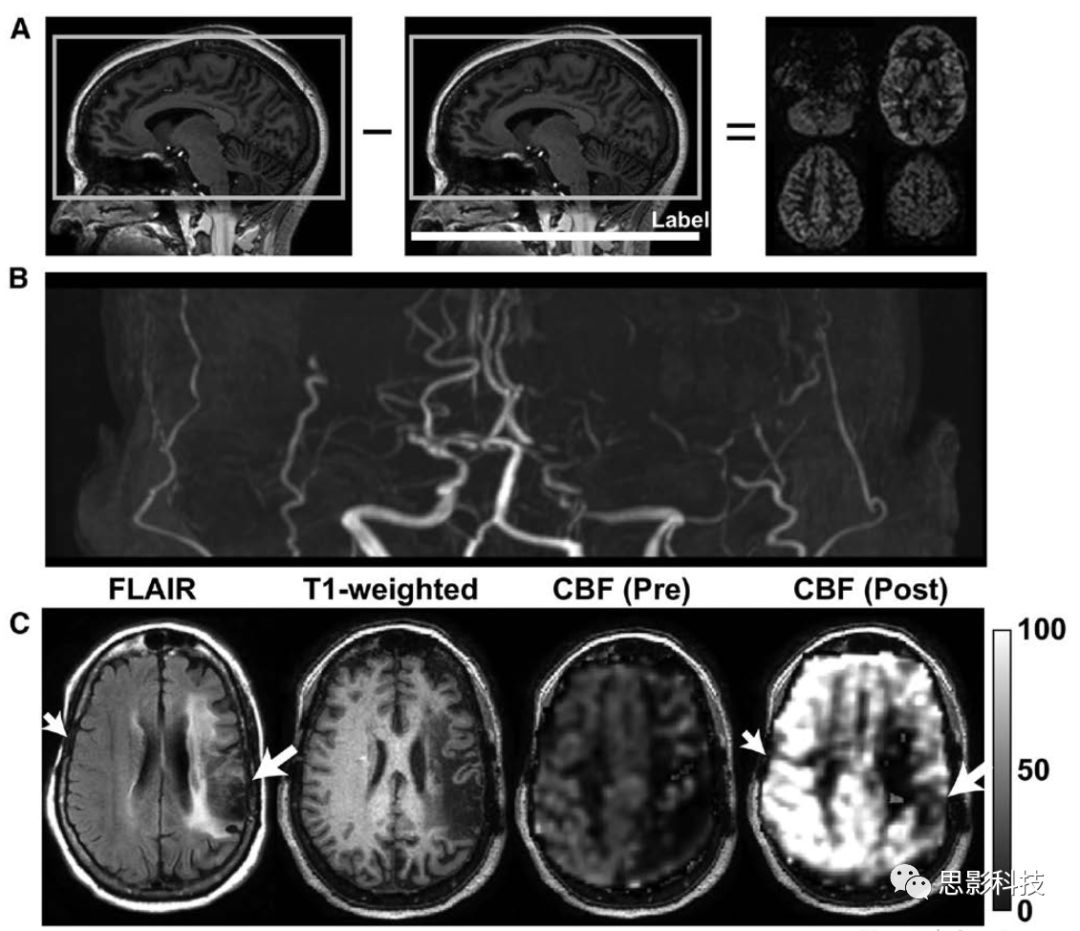

1動脈自旋標記磁共振成像(ASL-MRI)監(jiān)測外科血管重建。A:在ASL-MRI中,使用單個(脈沖或連續(xù)的)或一系列(偽連續(xù)的)射頻脈沖對血液進行磁性標記,之后反轉(zhuǎn)的血液流入成像層面的毛細血管,與組織液交換,并衰減血管外水信號。通過將該圖像與其中未標記血液的圖像進行比較,可以獲得灌注加權(quán)圖。B:煙霧病合并左側(cè)頸內(nèi)動脈床突上段閉塞、右側(cè)頸內(nèi)動脈遠端局灶性狹窄和雙側(cè)大腦中動脈閉塞患者的飛行時間磁共振血管成像。

C:雙側(cè)腦硬膜動脈貼敷術前后(左后22個月,右后16個月)ASL-MRI顯示術后腦血流量(CBF)改善情況。FLAIR:流體衰減反轉(zhuǎn)恢復。

越來越多的兒童使用ASL-MRI測量組織水平的CBF(圖1),可一致地顯示大腦中、前動脈區(qū)域的低灌注模式,且常伴有后灌注。煙霧病的ASL結(jié)果非常復雜,因為血液到達時間很長,根據(jù)成像參數(shù)的不同,可以表現(xiàn)為沒有信號或高信號。當CMRO2的影響可忽略或發(fā)生微小變化時,CBF增加,毛細血管和靜脈內(nèi)和周圍順磁性脫氧血紅蛋白相對于抗磁性氧合血紅蛋白的比例將減少,從而延長周圍水T2和T2*,增加MRI信號(即血氧水平依賴[BOLD]效應)。因此,T2*加權(quán)序列可用于在影響血液和組織中二氧化碳和pH水平的代謝時進行腦血管反應性繪圖:使用藥物誘導的碳酸酐酶抑制劑(如乙酰唑胺)或呼吸刺激(如高碳酸血癥)。腦血管反應性可能比基礎CBF更能預測預后,因為它表明組織實質(zhì)對灌注壓力變化作出反應的能力。該方法已應用于兒童煙霧病血管病變。